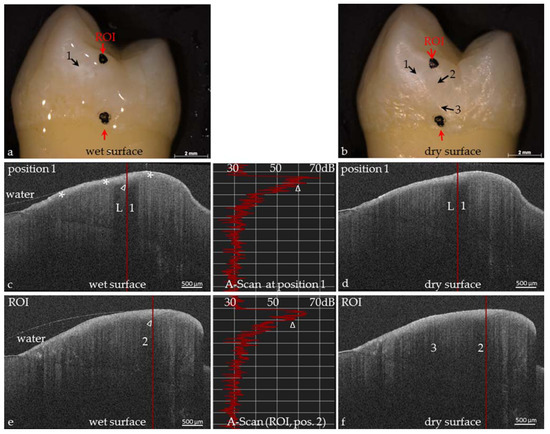

Figure 11. Extracted human premolar with early proximal demineralizations. There is a partial match of the visual and OCT assessment. (a) Hardly visible on wet enamel, the early demineralization (1) could also be seen on the dry surface (b); (cf) SD-OCT reveals a clinically invisible demineralization in the outer enamel zone (*); (c,d) The OCT images reveal a bright signal in position 1 (L, shadow); (e) The OCT of the wet surface shows an early demineralization in position 2 of image (b); (f) After air drying, an additional signal arises in position 3. Visually both lesions are invisible (a,b). With the knowledge of the OCT images, at points 2 and 3, slight opacities could also be anticipated on the images (a,b). The A-scans (average 5) of the marked positions 1 and 2 in the OCT-images demonstrate the depth profiles of the demineralized zones of the enamel surface. Δ grey scales between demineralized and healthy region.

The International Caries Detection and Assessment System in combination with radiography is insensitive to early caries detection. This has been confirmed by a number of the authors’ own OCT evaluations of apparently sound enamel surfaces (ICDAS II Code 0), particularly in cross-sectional OCT images where early stages of decay can often be detected without any clinical findings (Figure 10 and Figure 11).